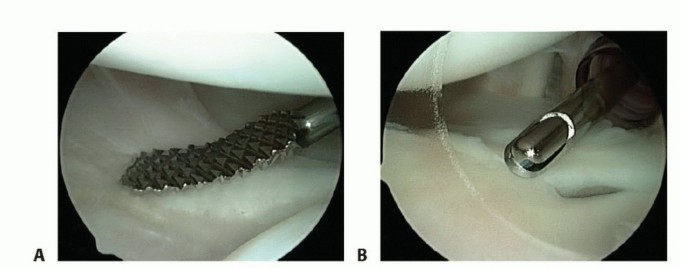

An arthroscopic rasp or chisel is used to mobilize any torn labrum from the glenoid rim (

TECH FIG 1A

).

A motorized synovial shaver or meniscal rasp is used to abrade the capsule adjacent to a labral tear and to débride and decorticate the glenoid rim to achieve a bleeding surface for capsular plication (

TECH FIG 1B

TECH FIG 1 • A. Rasping capsule to stimulate healing after capsular plication. B. Capsular/glenoid abrasion with a motorized shaver.